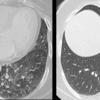

CT supine and prone

Date: 07/27/2013

Views: 3202